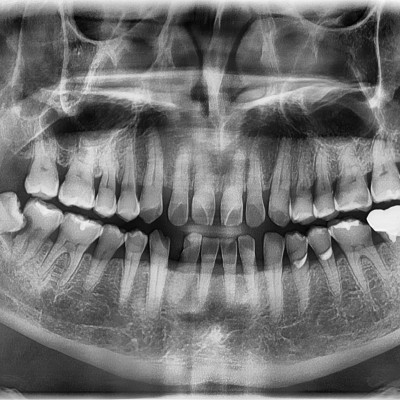

#18,28,38,48 사랑니 발치 #18,28,38,48 사랑니 발치 구강 외과 전문의가 당일 발치했습니다. --------------------..

작성자 이턱이 작성일 01-30 조회 15